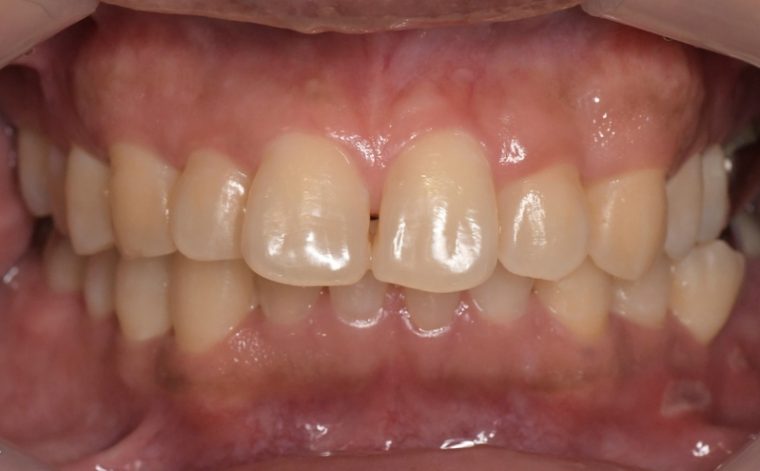

重度歯周病

特徴

歯周炎の段階です。

• 歯がグラつく、抜け落ちそう

• 歯ぐきからの出血が長期間、またはずっと続く

• 歯ぐきから膿がでる

• 口臭が強い

• 歯ぐきが下がって歯と歯の隙間が目立つ

重度歯周病の歯ぐきの写真

歯科医院でのクリーニング、歯ぐきを切開しておこなう歯石除去や歯の骨を補填する手術などあらゆる治療方法を用いて治療をおこないます。歯を残すことは前提ですが、リスクになりうる歯を抜歯するご相談をおこなうこともあります。

グラグラになった歯にブラシの毛先を当て磨くことは簡単ではありません。また歯ぐきの中に入り込んだ汚れは歯ブラシで取りきることができないため歯科医院での歯周病治療、クリーニングを受けるようにしましょう。